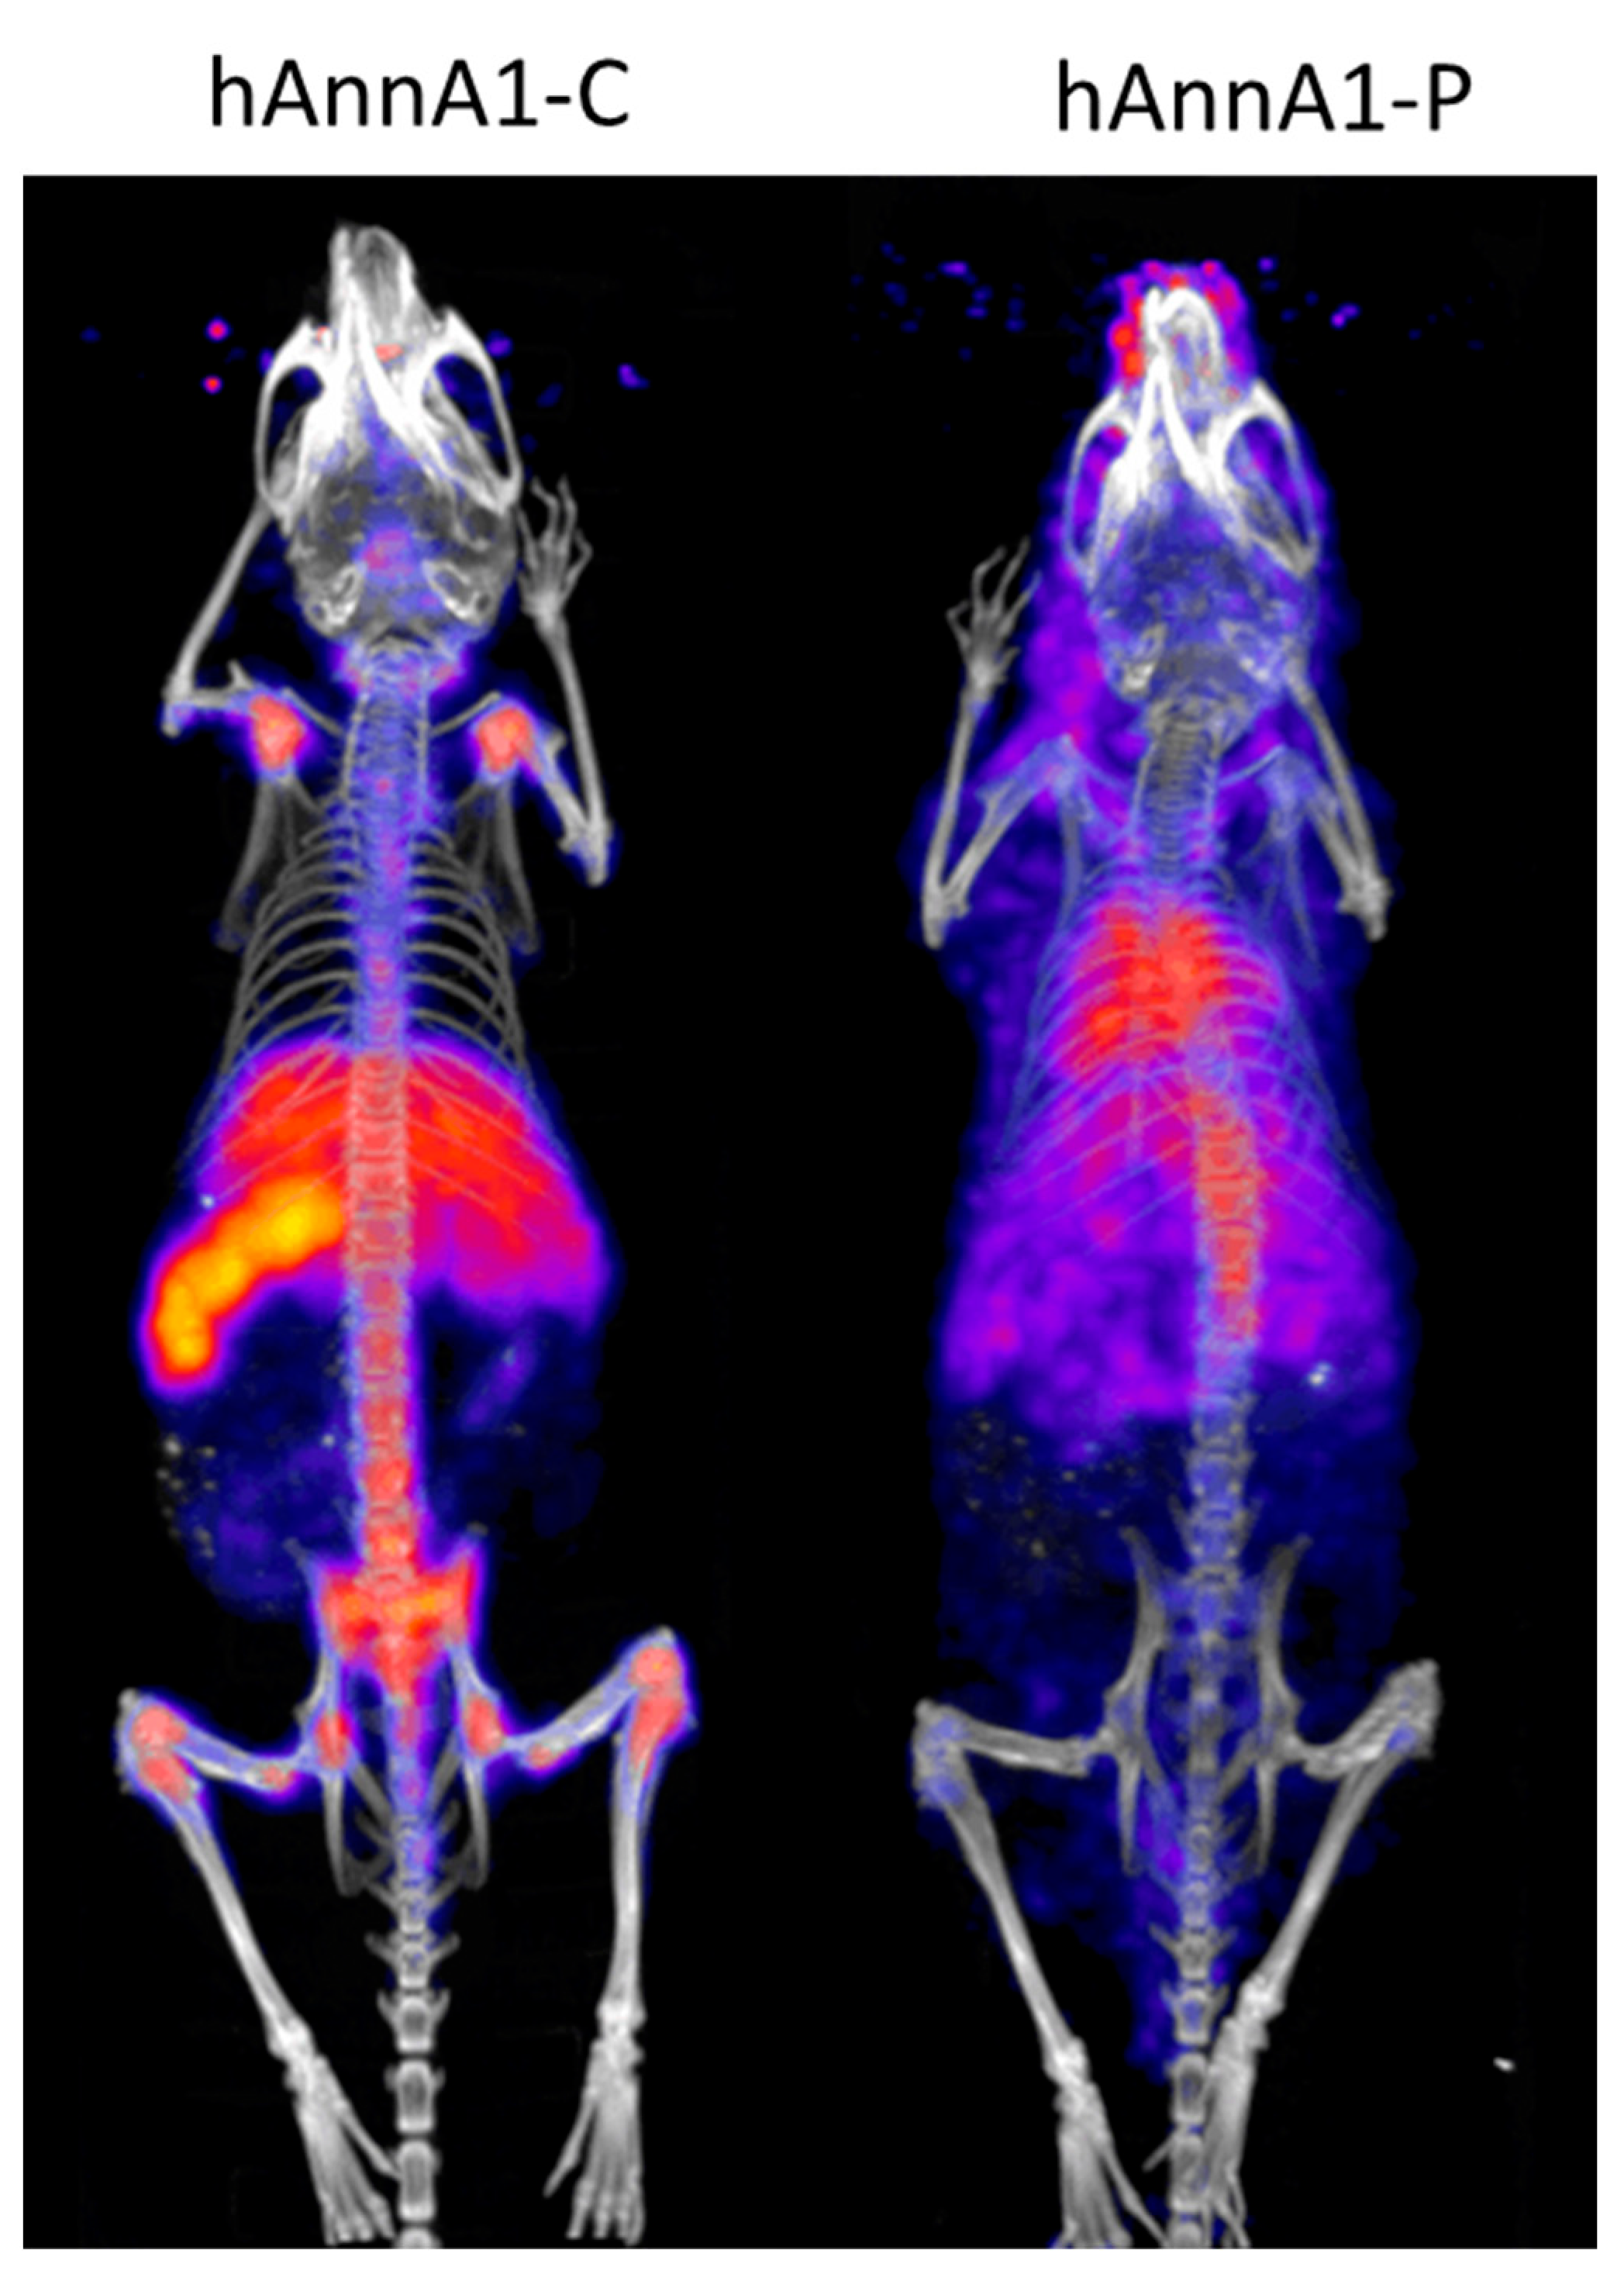

2. Results